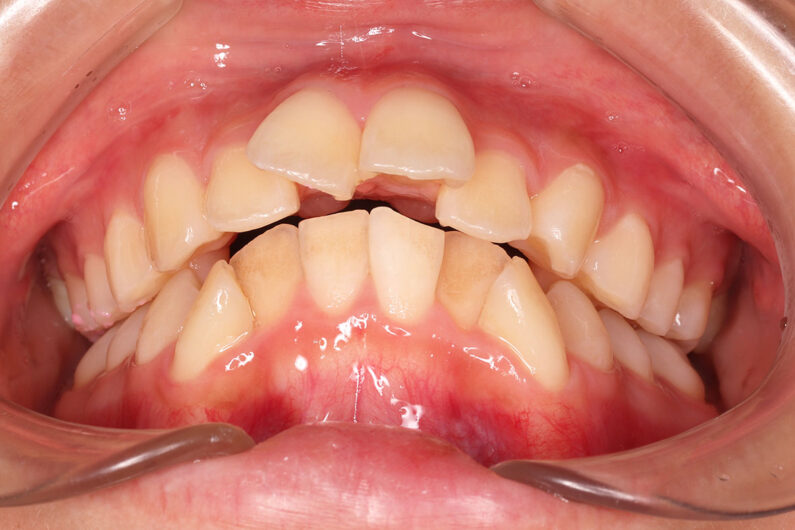

他院から紹介の患者さんです。 前歯、下の歯のガタツキをきれいにしたいということで治療を決断されました。

上顎前歯6mm、下顎前歯2.5mmの前突の状態で、口唇も前突しています。 小臼歯抜歯したスペースを使い、叢生(がたつき)と前突した前歯の後退を目標にしました。 この方も希望により、アンカースクリューは使用せず、通常の顎間ゴムで対処してもらいました。